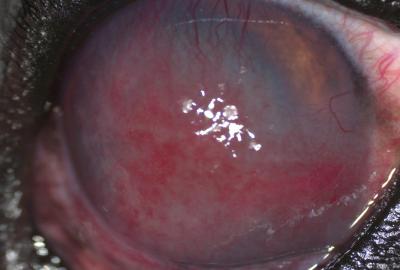

Vřed rohovky (melting ulcer) | Veterinární klinika Medipet Zlín